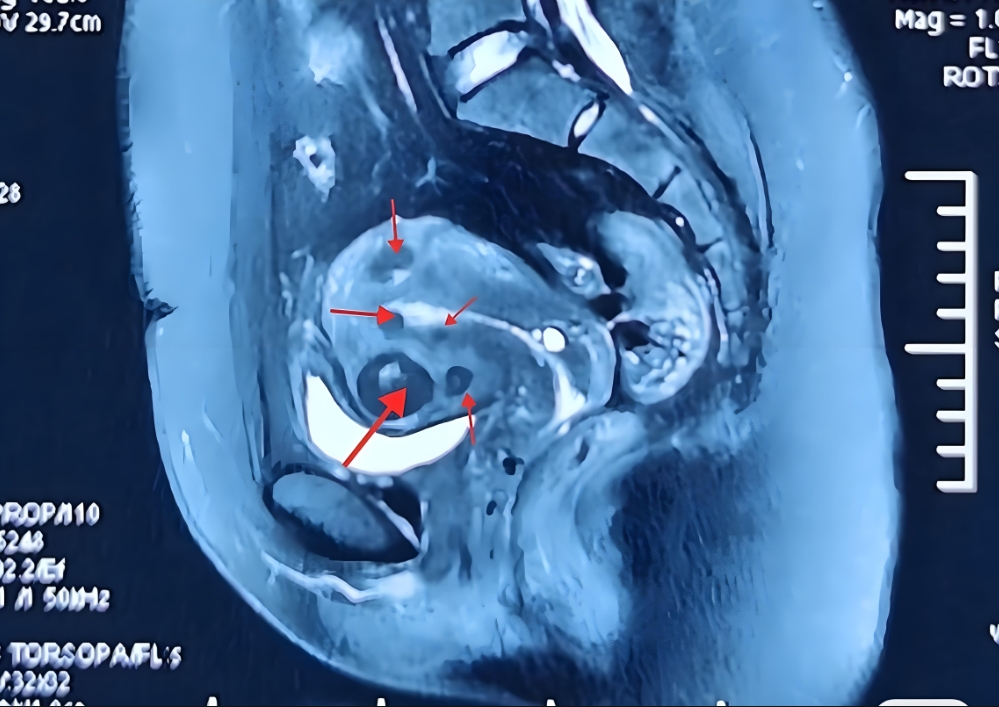

美国HRC的助孕技术优势显著,3D超声联合MRI精准定位肌瘤,血管热成像技术避免术中出血,像给医生配备“透视眼”,清晰看到肌瘤位置、大小及周围血管分布,减少出血风险。